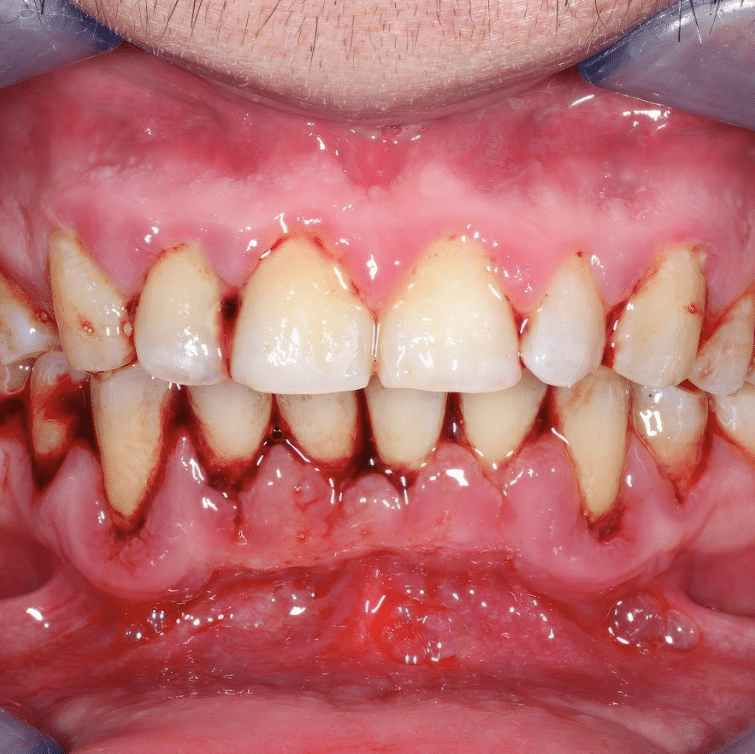

• Scaling and polishing: Scaling and polishing usually involves the thorough removal of plaque and tartar from your teeth. While its primary focus is maintaining oral health, it can also help eliminate some extrinsic stains and leave your teeth feeling incredibly clean and refreshed.